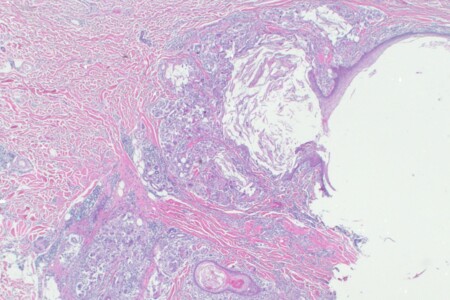

Opar, odborně herpes je infekční onemocnění kůže a sliznic, které patří k celosvětově nejrozšířenějším infekcím, postihujícím lidi všech věkových kategorií, bez rozdílu pohlaví nebo rasy. Opary jsou způsobeny herpetickými viry, které při aktivaci vytváří na kůži nevzhledné, puchýřnaté onemocnění, jenž bývá provázeno silnou bolestivostí. Ačkoliv je skupina herpetických virů početná, obsahuje osm virů způsobujících mnohdy zcela rozlišná onemocnění, blíže si popíšeme jen některé z nich. Původcem, toho veřejnosti dobře známého oparu je virus herpes simplex, který se vyskytuje ve dvou variantách HSV I a HSV II. HSV I neboli herpes simplex virus 1. typu je zodpovědný převážně za vznik oparu na rtu. Druhý typ viru způsobuje infekce v oblasti genitálu a konečníku, které označujeme jako genitální opar. Do skupiny lidských herpetických virů patří také Varicella zoster virus způsobující pásový opar.

Běžný opar rtu či genitálu je puchýřnaté onemocnění, které se objevuje na kůži či sliznici. Má podobu drobných vřídků naplněných tekutinou, které praskají a zasychají ve stroupky. Po inkubační době (2-6 dní) a po působení zmíněných provokačních faktorů vzniká v postiženém místě pocit napětí, svědění nebo pálení, někdy i bolest. Následně vznikne zarudnutí s otokem. Na takto změněné kůži nebo sliznici se vytvoří drobné napnuté puchýřky velikosti špendlíkové hlavičky. Po jejich prasknutí vznikají drobné eroze nebo zaschnou v strup, který po několika dnech odpadne. Onemocnění častokrát po 10-14 dnech ustoupí. Oparové infekce však mohou probíhat i dramaticky, obzvláště u první infekce mohou být příznaky masivnější a rozsáhlejší. Ložisko může postihovat i celý ret nebo dutinu ústní a to masivnějším otokem a výsevem puchýřků se současným zduřením lymfatických uzlin, někdy i celkovou alterací organismu.